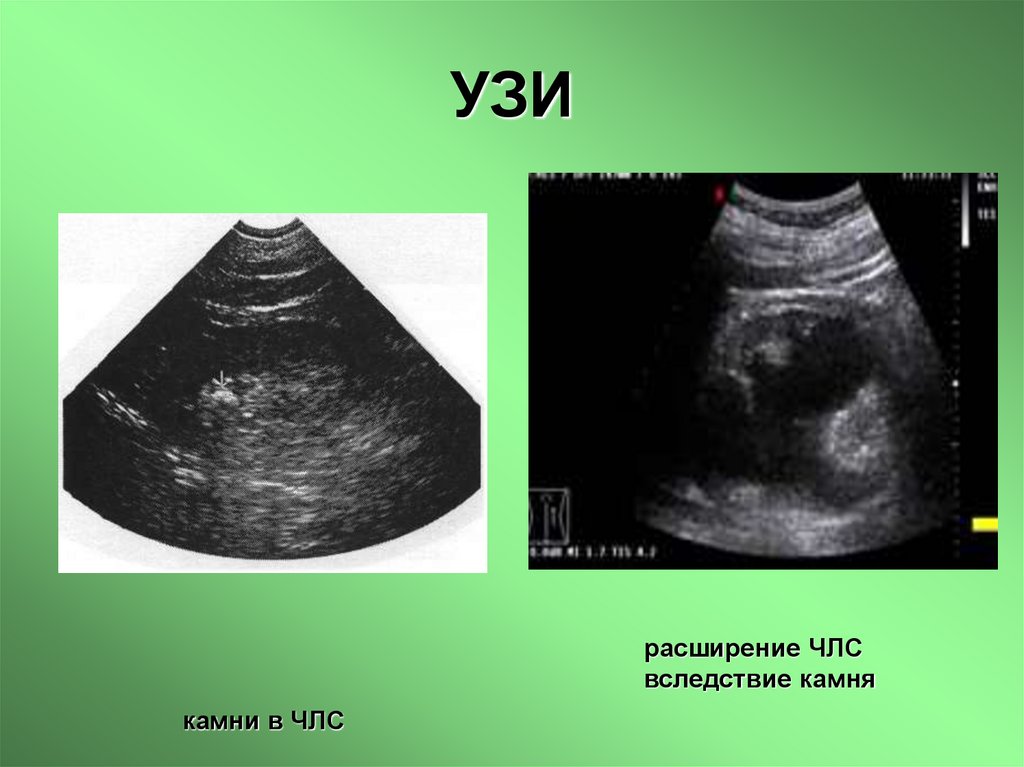

19. УЗИ

расширение ЧЛС

вследствие камня

камни в ЧЛС